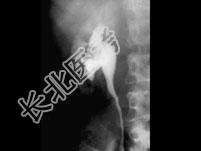

- 单项选择题男,74岁, 间歇性无痛性全程血尿2月余,尿路造影及CT平扫+增强如图所示, 下列说法错误的是 ( )

A、尿路造影示右侧肾盂内不规则的充盈缺损征象